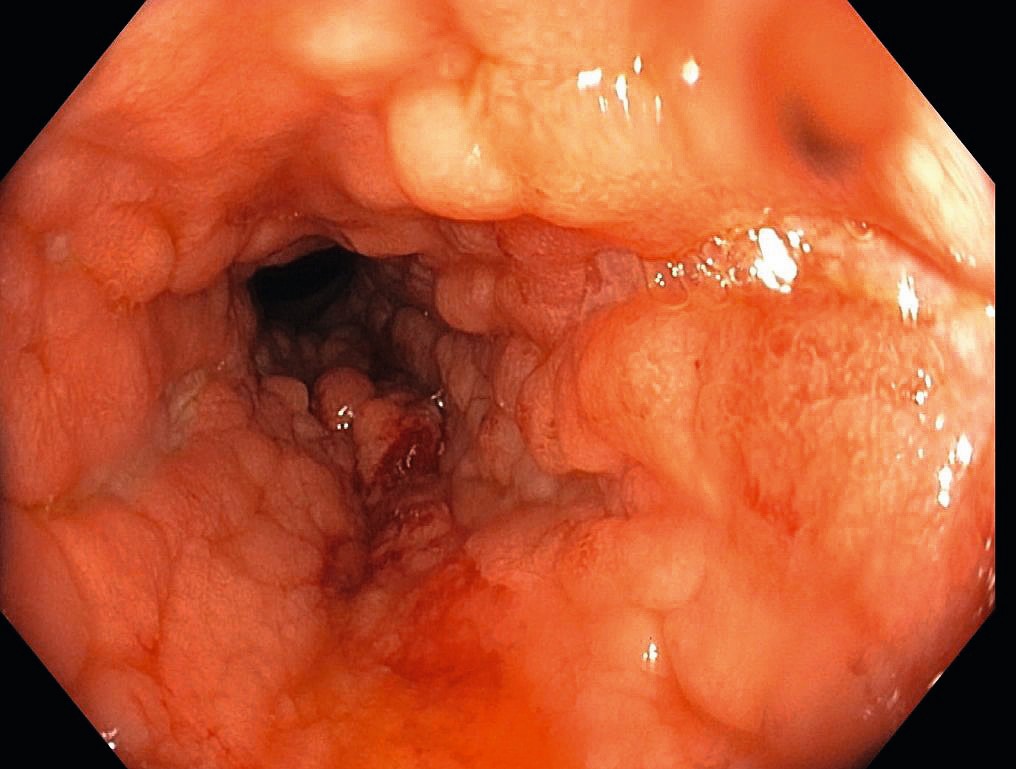

Im nächsten Schritt sollen eine Ileokoloskopie und auch eine Ösophagusgastroduodenoskopie durchgeführt werden. Von großer Bedeutung ist dabei die makroskopische Beurteilung der Schleimhaut mit Augenmerk auf Crohn-spezifische Veränderungen wie einen diskontinuierlichen Befall und fissurale Ulzerationen [16]. Die Beschreibung der Lokalisation und des Schweregrades der Entzündung sind für den weiteren Verlauf und die Therapie von zentraler Bedeutung. Außerdem sollten Stufenbiopsien aus dem Bereich des Ileums sowie des Colons und des Rektums zur weiterführenden histopathologischen Begutachtung gewonnen werden. Da der Morbus Crohn im gesamten Gastrointestinaltrakt auftreten kann, wird insbesondere bei Erstdiagnose und im Verlauf je nach Symptomatik eine Ösophagogastroduodenoskopie empfohlen. Grundlage für diese Empfehlungen in der Deutschen Leitlinie ist eine hohe Anzahl an Morbus Crohn-Patienten mit Magenbefall [17]. Die Durchführung einer MRT Enterografie (Sellink) ist zur Beurteilung des mittleren Gastrointestinaltrakts indiziert (Goldstandard) und sollte bei Erstdiagnose eines Morbus Crohn durchgeführt werden. Die Darmsonografie bietet bei entsprechender Expertise ein praktisch gleichwertiges diagnostisches Mittel (da annähernd gleich hohe Sensitivität) in der Beurteilung einer Dünndarmbeteiligung, wobei auch das Colon gut beurteilt werden kann [18]. Die Kapselendoskopie kann im Einzelfall bei unschlüssigen Befunden (erhöhtes CRP/Calprotectin, unklare Eisenmangelanämie) und fortbestehendem Verdacht auf eine Dünndarmmanifestation durchgeführt werden (keine allgemeine GKV-Leistung, nur bei unklarer Anämie und unklarer Befundkonstellation nach unauffälliger Gastroskopie und Ileo-Koloskopie) [19]. Die Ballon-Enteroskopie wird gelegentlich diagnostisch zur Gewinnung von Gewebeproben bei isolierter Dünndarmerkrankung zur Diagnossicherung oder zum Ausschluss anderer Entzündungsursachen und von Neoplasien, häufiger aber therapeutisch zur Dilatation von Stenosen angewandt. Bei Verdacht auf extramurale Komplikationen, wie zum Beispiel Abszesse oder Fisteln, sind je nach Lokalisation eine MRT-Enterografie, ein MRT des Beckens, eine transrektale Endosonografie sowie die Darmsonografie Mittel der Wahl [18].